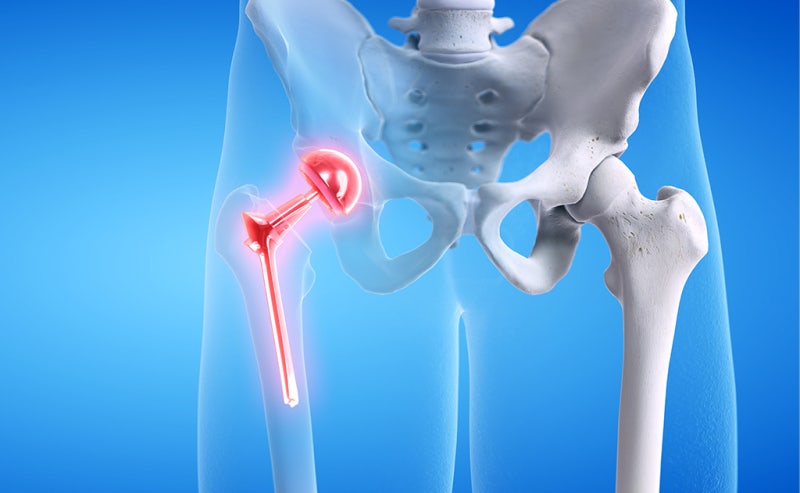

- 인공관절 치환술: 가장 일반적인 고관절 수술입니다. 퇴행성 관절염이나 심한 외상으로 인해 고관절이 손상된 경우, 인공 관절로 대체합니다. 이 수술은 대개 1-2시간 가량 소요되며, 회복이 길어질 수 있습니다.

고관절 수술은 다양한 이유로 시행될 수 있지만, 일반적으로는 고관절 관절염, 외상, 또는 선천적인 기형 등으로 인해 통증이나 기능 저하가 나타날 때 이루어집니다. 이 수술에는 인공관절 치환술, 관절경 수술 등의 방법이 있으며, 각각의 수술 방법은 회복 단계와 필요한 시간에 서로 영향을 미칩니다. 고관절 수술의 주된 목적은 통증을 감소시키고, 이동성과 일상생활의 질을 향상시키는 것입니다. 그러므로, 환자는 수술 후 생활 습관을 조절하고, 적극적인 rehabilitative 간호를 통해 빠른 회복을 도모해야 합니다.